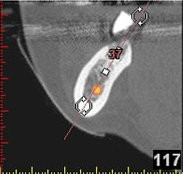

In komplexen Fällen, z. B. der Implantatversorgung eines kompletten Kiefers, oder bei schwierigen Knochensituationen bietet die 3-dimensionale Computerdiagnostik bzw. Planung und Durchführung erhebliche Vorteile und Sicherheit für den Patienten (siehe Bild 1 und 2).

3D-Implantatplanung - Detailaufnahme 1

Auf Basis einer computertomografischen (CT-) Kieferaufnahme ist eine dreidimensionale Darstellung der Knochen möglich. Der Zahnarzt kann dann am Computerbildschirm die Knochenqualität (z. B. Knochendichte) beurteilen und die optimale Position der Implantate im Vorfeld planen. Durch Verwendung spezieller Röntgenschablonen lässt sich auch die erwünschte Zahnstellung in die Planung einbeziehen. Die Simulation der OP erlaubt, das zu erwartende Ergebnis mit größtmöglicher Sicherheit vorherzusagen und dem Patienten am Bildschirm zu veranschaulichen.

(siehe Bild 3 und 4).